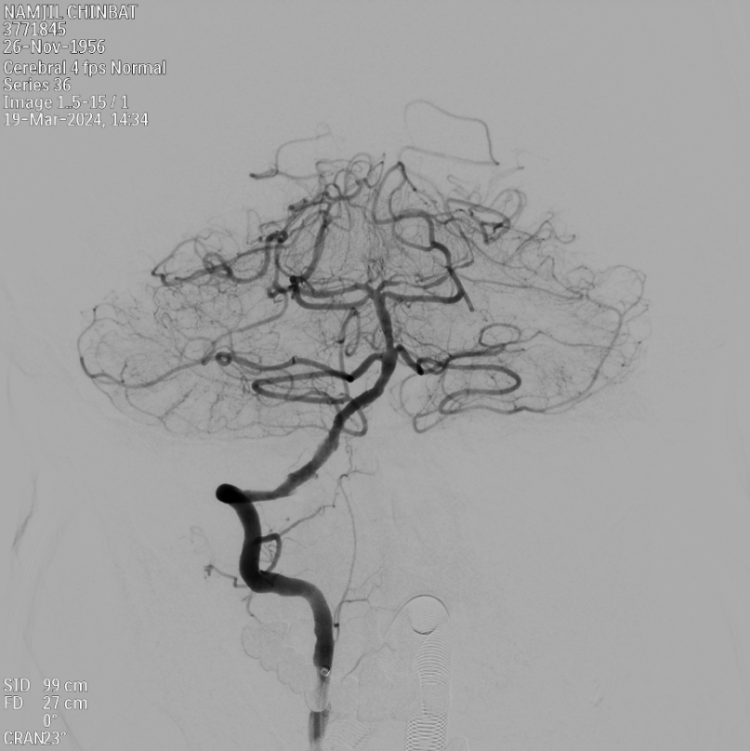

经过了严谨的多学科术前讨论,万杰清制定了详细的手术方案:穿刺双侧股动脉,双路径图下指引开通方向,术中微导丝探路直至闭塞远端血管、用颅内专用球囊和支架开通血管;术后适当延长麻醉复苏时间,严格控制血压预防脑组织高灌注出血。

手术当天,在麻醉科主治医师林雨轩、导管室护士长韦兆玲和DSA技师管逊的全力配合下,万杰清和神经外科副主任医师丁圣豪按预定方案从容施行手术。这位病人的右侧椎动脉从入颅段就完全闭塞了,远端的血管路径不清,整个再通血管的过程就像是“重新打通坍塌的隧道”。

只见微导丝如白驹过隙通过了闭塞血管,球囊扩张、支架成型等操作一气呵成。从远到近一路塑形,顺利打通了整个闭塞段血管。转眼间,血供恢复,患者的生命之路被打通了。